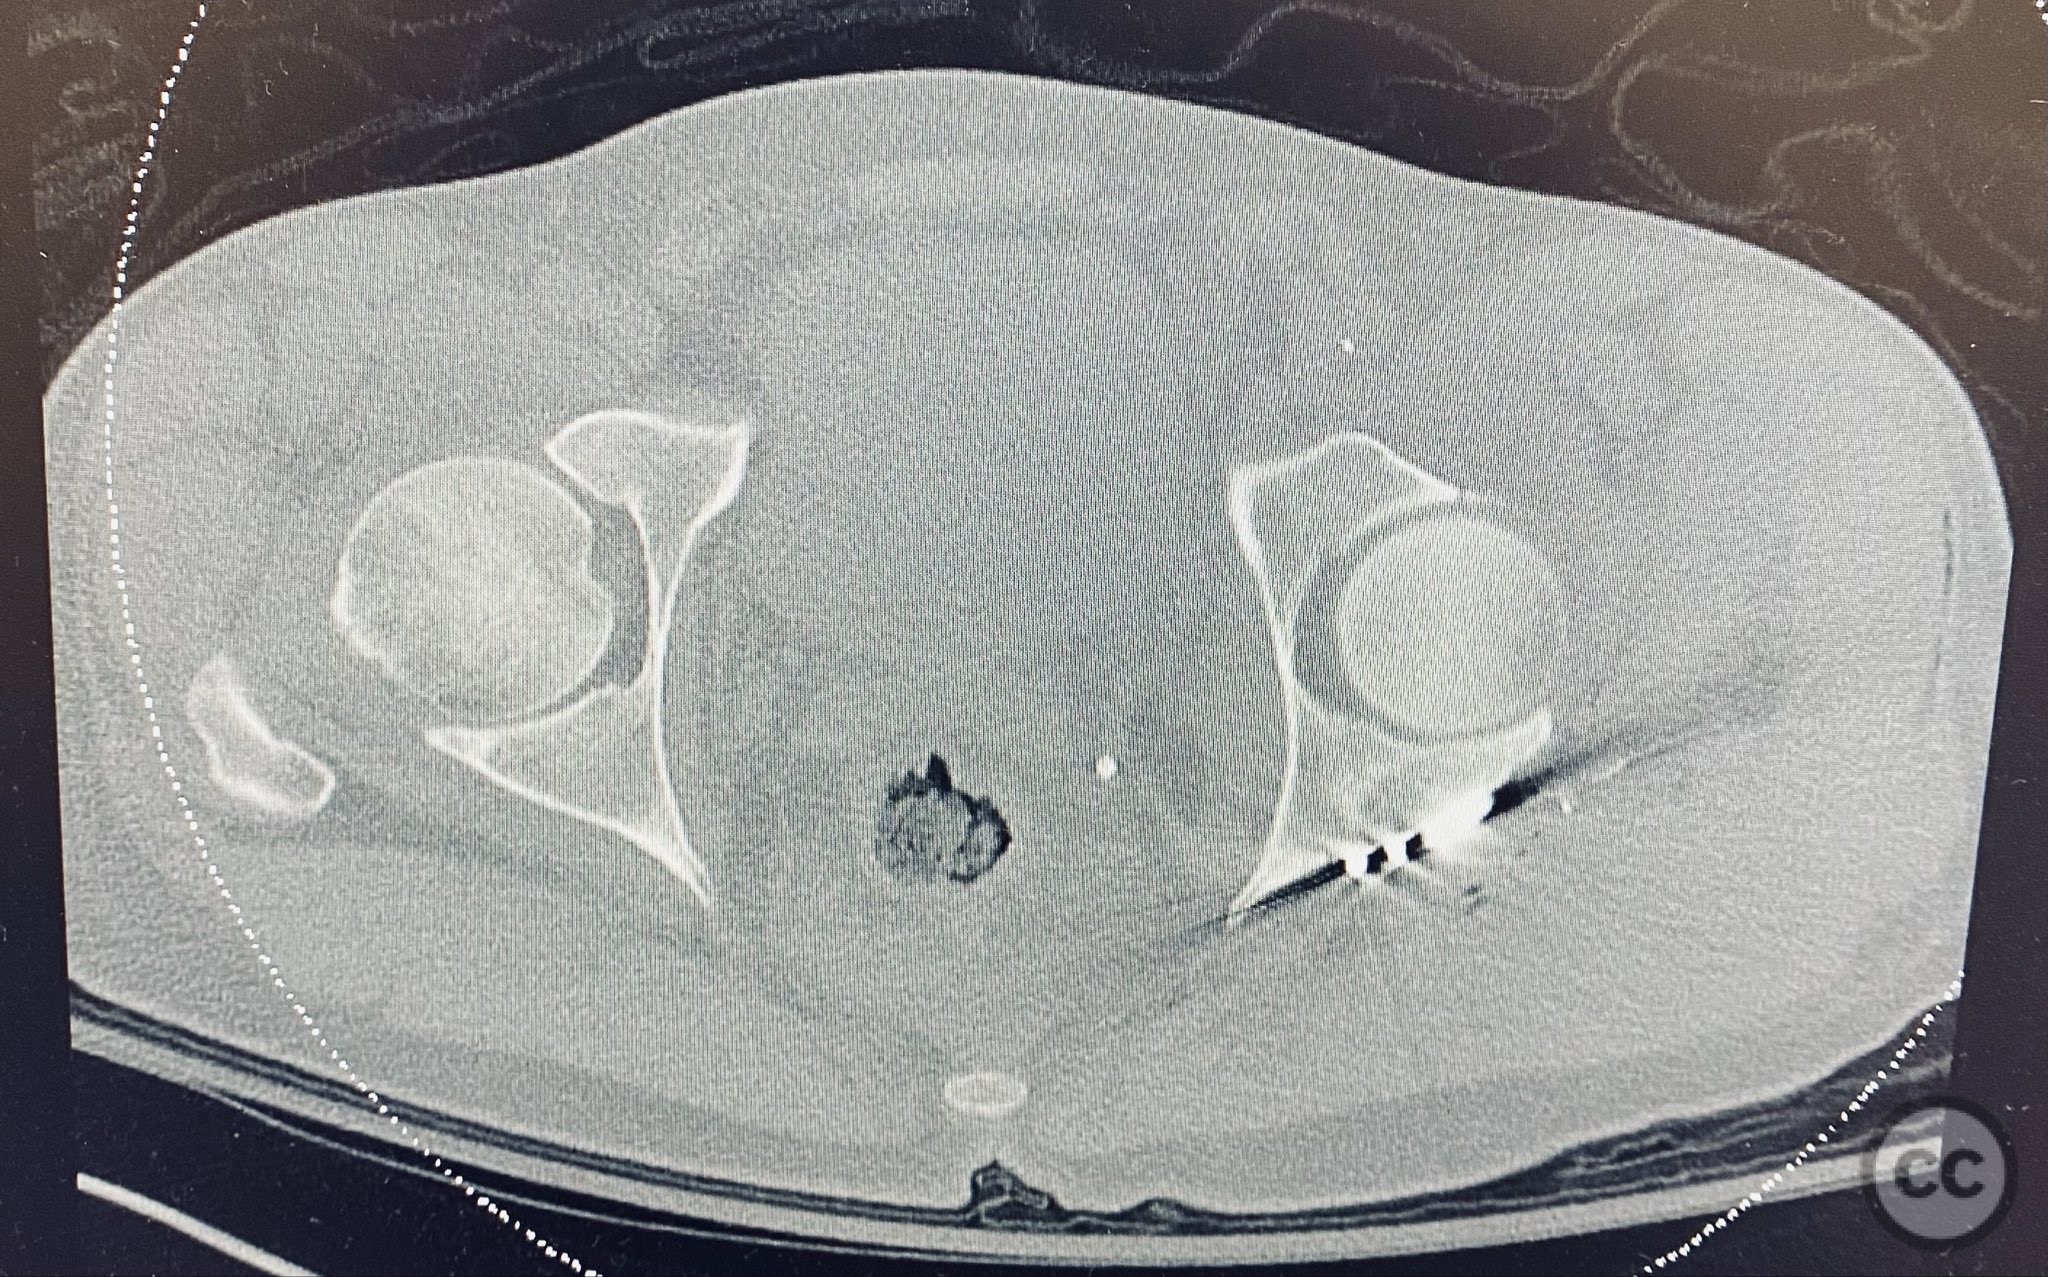

Clinical and radiological findings:  A patient presented with a seemingly non-comminuted, wide, and long posterior wall (PW) acetabular fracture fragment. Axial computed tomography (CT) images demonstrated the thickness of the PW fragment, the articular surface, and multiple areas of subchondral impaction. Preoperative planning identified the size, location, and depth of the impaction zones, as well as an essentially nondisplaced transverse acetabular fracture line, which was not readily apparent on initial imaging. No significant displacement of the transverse component was noted. The AO/OTA classification is 62-B1.3 (posterior wall and transverse acetabular fracture).

Intraoperatively, elevation and reduction of impacted articular fragments were performed, followed by bone grafting of subchondral defects. The posterior wall fragment was anatomically reduced and initially stabilized with a contoured plate. Intraoperative fluoroscopy (obturator oblique view) was utilized to guide placement of an additional screw through the plate above the joint, traversing both the posterior wall fragment and stabilizing the transverse fracture line. A supplementary medial plate was applied to further support both fracture components. Postoperative CT imaging confirmed satisfactory reduction of both the posterior wall and transverse fractures, as well as restoration of articular congruity in previously impacted areas. Consideration is given to whether initial reduction and lag screw fixation of the transverse component prior to plate application may have improved reduction; however, final imaging demonstrated acceptable alignment.